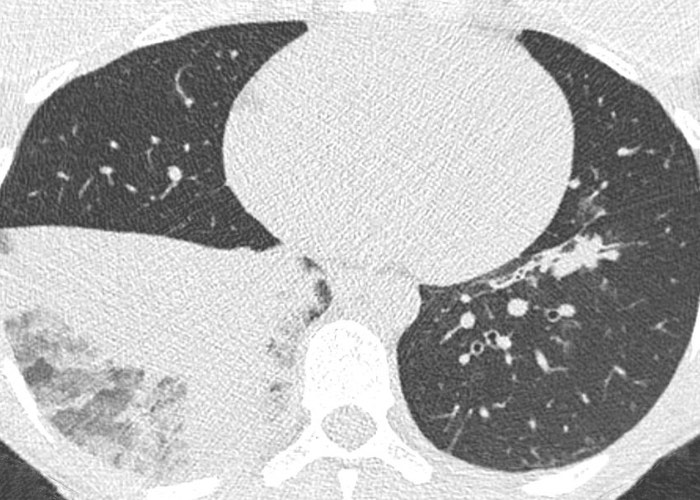

| broncho-pneumonie | condensations péribronchovasc + micro-macronodulation confluente (staph, haemophilus, pseudomonas, E. coli, grippe) |  |

| embolies septiques | condensations nodulaires ±excavées (staph, pyo, candida, BK, Lemierre) |  |